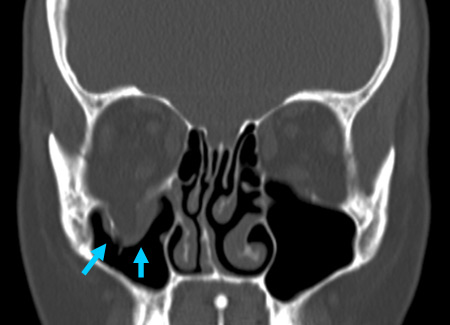

Right orbital blow-out fracture on CT-scan; coronal reformat

From the personal collection of Dr Alistair Cobb